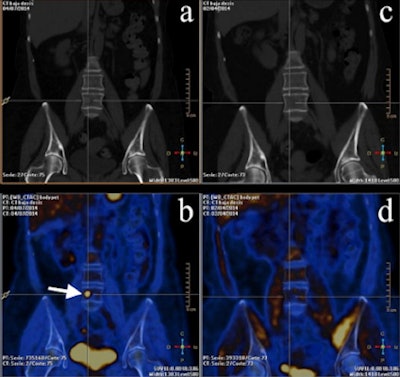

PET/CT images from a 53-year-old woman with breast cancer in the course of therapy but with rising biomarkers. (a, b) PET/CT images midtherapy. (c, d) Basal PET/CT images. Bone M1 can only be seen with FDG-PET. Images courtesy of Dr. José Vercher-Conejero.

PET/CT images from a 53-year-old woman with breast cancer in the course of therapy but with rising biomarkers. (a, b) PET/CT images midtherapy. (c, d) Basal PET/CT images. Bone M1 can only be seen with FDG-PET. Images courtesy of Dr. José Vercher-Conejero.Future directions